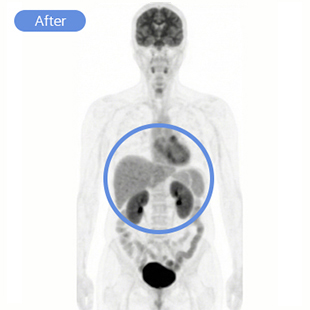

현재상태 2025. 05 ~ , 현재NED(암 병변 없음) 8개월차 / 재발방지치료 중

대학병원 항암화학요법 - FOLFOX

리움한방병원 싸이모신알파원, 미슬토, 고용량셀레늄, 고주파온열치료(BSD-2000), 항암단, 건칠정